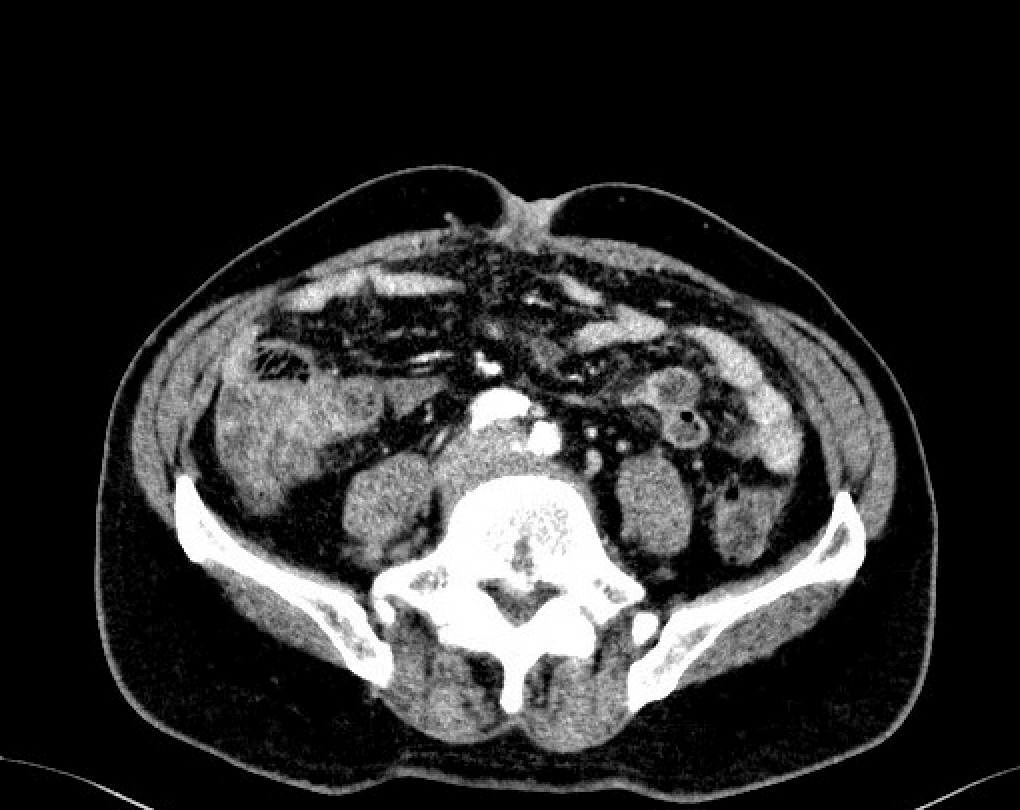

En 78-årig mand oplevede igennem længere tid tilstedeværelsen af en hård, rødlig og let kløende udfyldning omkring navlen. Han havde været i behandling for både svamp og eksem uden effekt. CT af abdomen viste dissemineret malignitet, herunder umbilikalmetastase samt peritoneal karcinose. Biopsi fra umbilikalmetastasen påviste adenokarcinom, og sammenholdt med skanningssvarene var diagnosen forenelig med primærtumor udgående fra pancreas. Patienten afgik ved døden, under to måneder efter at diagnosen var stillet, på trods af kemoterapi.

Sister Mary Joseph-nodulus er en umbilikalmetastase forbundet med gastrointestinal malignitet [1], og tilstedeværelsen af denne nodulus tyder ofte på en fremskreden cancer med en dårlig prognose [2]. Dette fænomen blev for første gang beskrevet i 1949, da sygeplejerske Sister Mary Joseph Dempsey observerede sammenhængen mellem umbilikale forandringer hos patienter med dissemineret gastrointestinal malignitet [3].